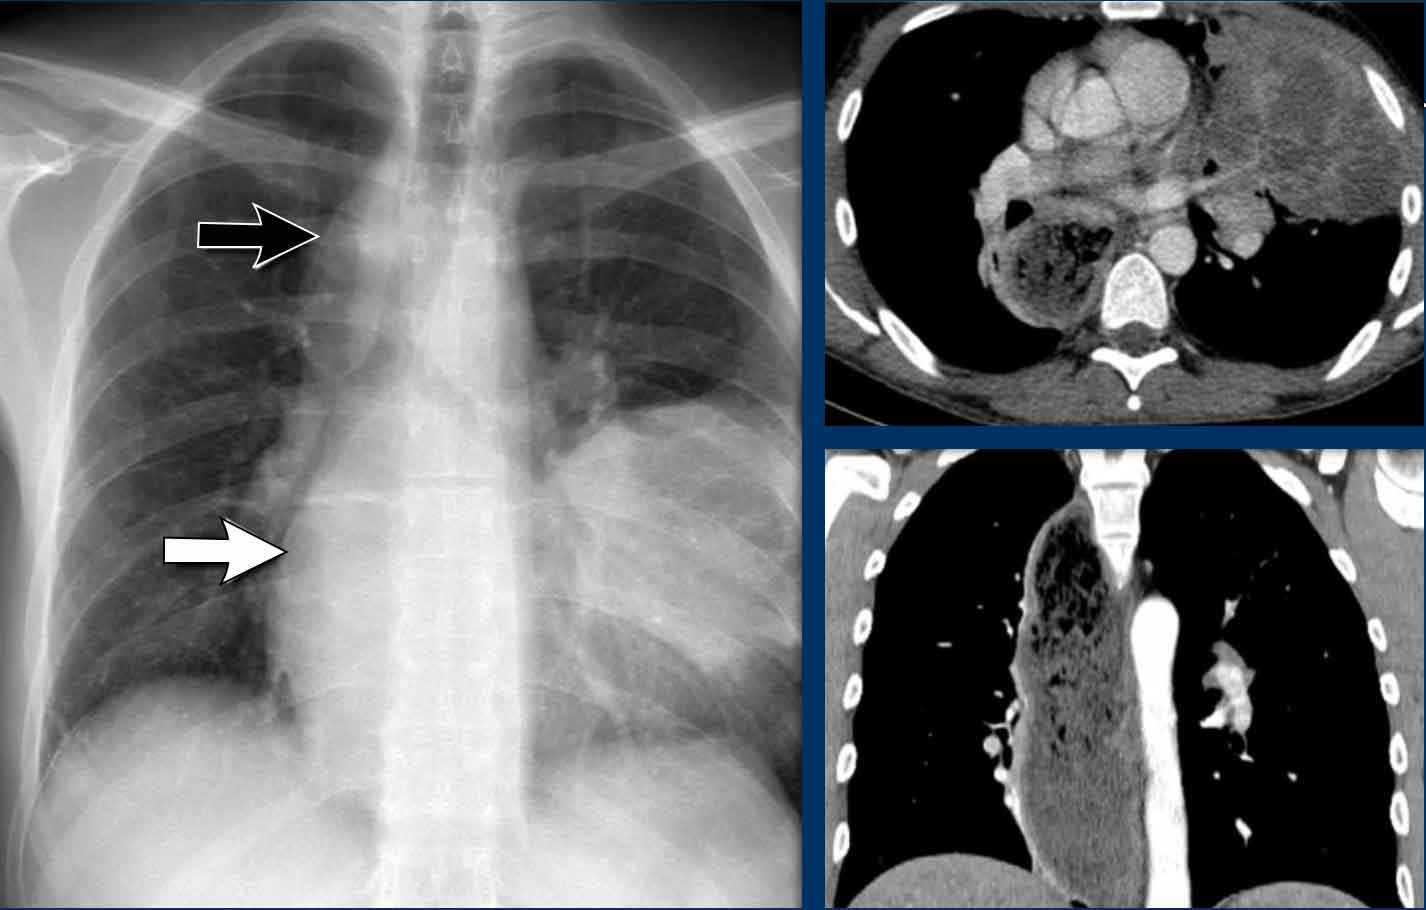

Displacement of the Azygoesophageal Line (2) – Subcarinal Lymphadenopathy

A common cause of displacement of the azygoesophageal line is subcarinal lymphadenopathy (station 7).

On the chest X-ray, note superior displacement of the azygoesophageal line just below the carina, consistent with enlarged subcarinal lymph nodes (black arrow).

Additional right paratracheal lymphadenopathy is seen, displacing the right paratracheal stripe (white arrow) and deviating the trachea to the left.

Continue with PET-CT...

PET Imaging

• PET-CT demonstrates extensive hypermetabolic lymphadenopathy in the mediastinum and neck, which is more conspicuous than on chest radiography.

• Cervical lymph nodes are involved—an important finding as they are accessible for biopsy.

Continue with images of CT and ultrasound...

CT Imaging

• Contrast-enhanced CT shows bulky subcarinal lymphadenopathy displacing the azygoesophageal recess and compressing the left atrium.

• Biopsy of a cervical node confirmed small cell lung carcinoma.